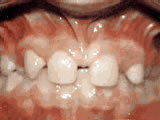

Crowding of the teeth

crowning of teeth

Before